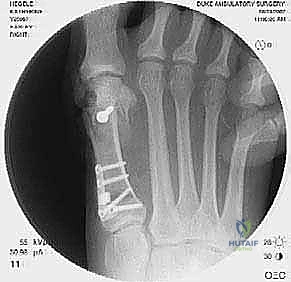

2. التصوير الشعاعي المتقدم

- الأشعة السينية مع تحمل الوزن (Weight-bearing X-rays): صور من الأمام، الجانب، والزوايا المائلة لتقييم زوايا العظام تحت تأثير وزن الجسم.

- تصوير السمسمانيات (Sesamoid view): لمعرفة ما إذا كانت العظام السمسمانية قد خُلعت من مكانها.

- الأشعة المقطعية (CT Scan): في الحالات المعقدة، يستخدم الدكتور هطيف الأشعة المقطعية ثلاثية الأبعاد لتقييم التئام العظام السابق، ومواقع المسامير القديمة، ودرجة خشونة المفاصل بدقة متناهية.

جراحة المراجعة هي عمل فني وهندسي معقد. إليك كيف يقوم الأستاذ الدكتور محمد هطيف بإجرائها خطوة بخطوة، معتمدًا على أحدث التقنيات العالمية:

- يتم تحديد مواقع المسامير أو الشرائح المعدنية من الجراحة السابقة وإزالتها (Hardware Removal). قد تكون هذه الخطوة صعبة إذا نما العظم فوق المسامير.

ب. عملية لابيدوس (Lapidus Procedure - TMTJ Arthrodesis)

إذا كان سبب التكرار هو "فرط الحركة" في مفصل منتصف القدم (TMTJ)، فإن الحل الوحيد لمنع التكرار المستقبلي هو دمج (إيثاق) هذا المفصل. يزيل الدكتور هطيف الغضروف من المفصل، يصحح زاوية العظم، ويثبته بشريحة معدنية قوية ومسامير حتى يلتحم العظمان معًا. هذه العملية تعالج أصل المشكلة من الجذور.

في هذه العملية، يتم إزالة الغضروف التالف من مفصل الإصبع الكبير، ودمج العظام معًا في وضع مستقيم قليلاً للأعلى للسماح بالمشي الطبيعي. يتم التثبيت باستخدام شريحة ومسامير متقاطعة. النتيجة هي إصبع مستقيم، خالٍ تمامًا من الألم، ولا يمكن أن يعود للتشوه أبدًا.